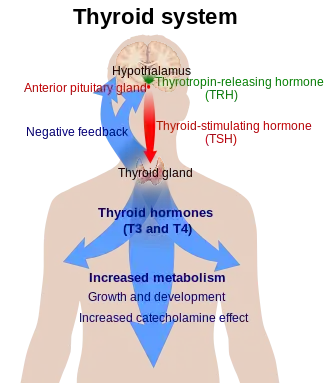

Thyroid disease is a medical condition that affects the function of the thyroid gland. The thyroid gland is located at the front of the neck and produces thyroid hormones[1] that travel through the blood to help regulate many other organs, meaning that it is an endocrine organ. These hormones normally act in the body to regulate energy use, infant development, and childhood development.[2]

There are several hormones that can be measured in the blood to determine how the thyroid gland is functioning. These include the thyroid hormones triiodothyronine (T3) and its precursor thyroxine (T4), which are produced by the thyroid gland. Thyroid-stimulating hormone (TSH) is another important hormone that is secreted by the anterior pituitary cells in the brain. Its primary function is to increase the production of T3 and T4 by the thyroid gland.

The most useful marker of thyroid gland function is serum thyroid-stimulating hormone (TSH) levels. TSH levels are determined by a classic negative feedback system in which high levels of T3 and T4 suppress the production of TSH, and low levels of T3 and T4 increase the production of TSH. TSH levels are thus often used by doctors as a screening test, where the first approach is to determine whether TSH is elevated, suppressed, or normal.[25]

- Elevated TSH levels can signify inadequate thyroid hormone production (hypothyroidism)

- Suppressed TSH levels can point to excessive thyroid hormone production (hyperthyroidism)

- To differentiate between different types of hypothyroidism, a specific test may be used. Thyrotropin-releasing hormone (TRH) is injected into the body through a vein. This hormone is naturally secreted by the hypothalamus and stimulates the pituitary gland. The pituitary responds by releasing thyroid-stimulating hormone (TSH). Large amounts of externally administered TRH can suppress the subsequent release of TSH. This amount of release-suppression is exaggerated in primary hypothyroidism, major depression, cocaine dependence, amphetamine dependence and chronic phencyclidine abuse. There is a failure to suppress in the manic phase of bipolar disorder.[28]